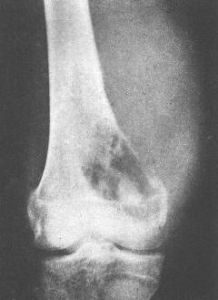

X線檢查可見腫瘤位於長骨幹骺端一側皮質表面,外形呈菜花狀、懸垂狀骨性骨塊,其尖端朝向鄰近關節相反方向。其基底直接或有一細蒂與骨皮質相連續。瘤體表面的軟骨帽雖然在X線上不顯影,但常有鈣化和骨化位於前臂、小腿的較大腫瘤可壓迫鄰近骨骼,產生壓迫性骨缺損或畸形。多發性者往往合併骨骼畸形。

1.X線表現:表現為附著於乾骺端的向外骨性突起,生長方向與肌肉的牽引方向一致,與受累骨皮質和松質骨相連,軟骨帽不顯影,有長蒂型和廣基型之分。